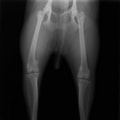

■ 症例20 ポメラニアン 8ヶ月 1.8kg

左右膝蓋骨脱臼 グレードⅢ

2ヶ月前から間欠的跛行が認められ、両膝の膝蓋骨脱臼整復術を行った。

手技は縫工筋及び内側広筋の解放、脛骨粗面の外側転位、滑車ブロック形造溝術、内外側関節包の縫縮を選択し実施した。

右側の膝蓋骨脱臼は上記手技で整復されたものの、左側はそれのみでは膝蓋骨が浮く様子が認められた。その為、PDS縫合糸にて膝蓋靱帯を1糸のみ縫合し、靱帯の縫縮を行った。

膝蓋骨脱臼は膝関節における膝蓋骨の内外側の脱臼と定義されるが、時として単純な内外の脱臼ではなく、膝蓋骨が大きく前方に浮き上がるように脱臼する場合がある。特にトイプードルやポメラニアンといった犬種に多く認められる。

内側脱臼に加えて前方への浮き上がりを矯正する為に、従来より脛骨粗面転移により膝蓋靭帯を外方と下方に引っ張り、固定する方法を選択する。膝蓋骨の前方への浮き上がりが軽度の場合は、従来法ではなく関節包の縫縮で対応していた。しかし、一部の症例で膝蓋骨の動きが悪くなり伸展機構が円滑に機能せずロボット様歩行になるケースがあった。

その為、膝蓋靭帯自体を縫縮する方法を採用した。この方法により、膝関節の伸展機構を妨げず膝蓋骨の軽度の浮きを矯正することが可能となった。

本症例の経過は良好である